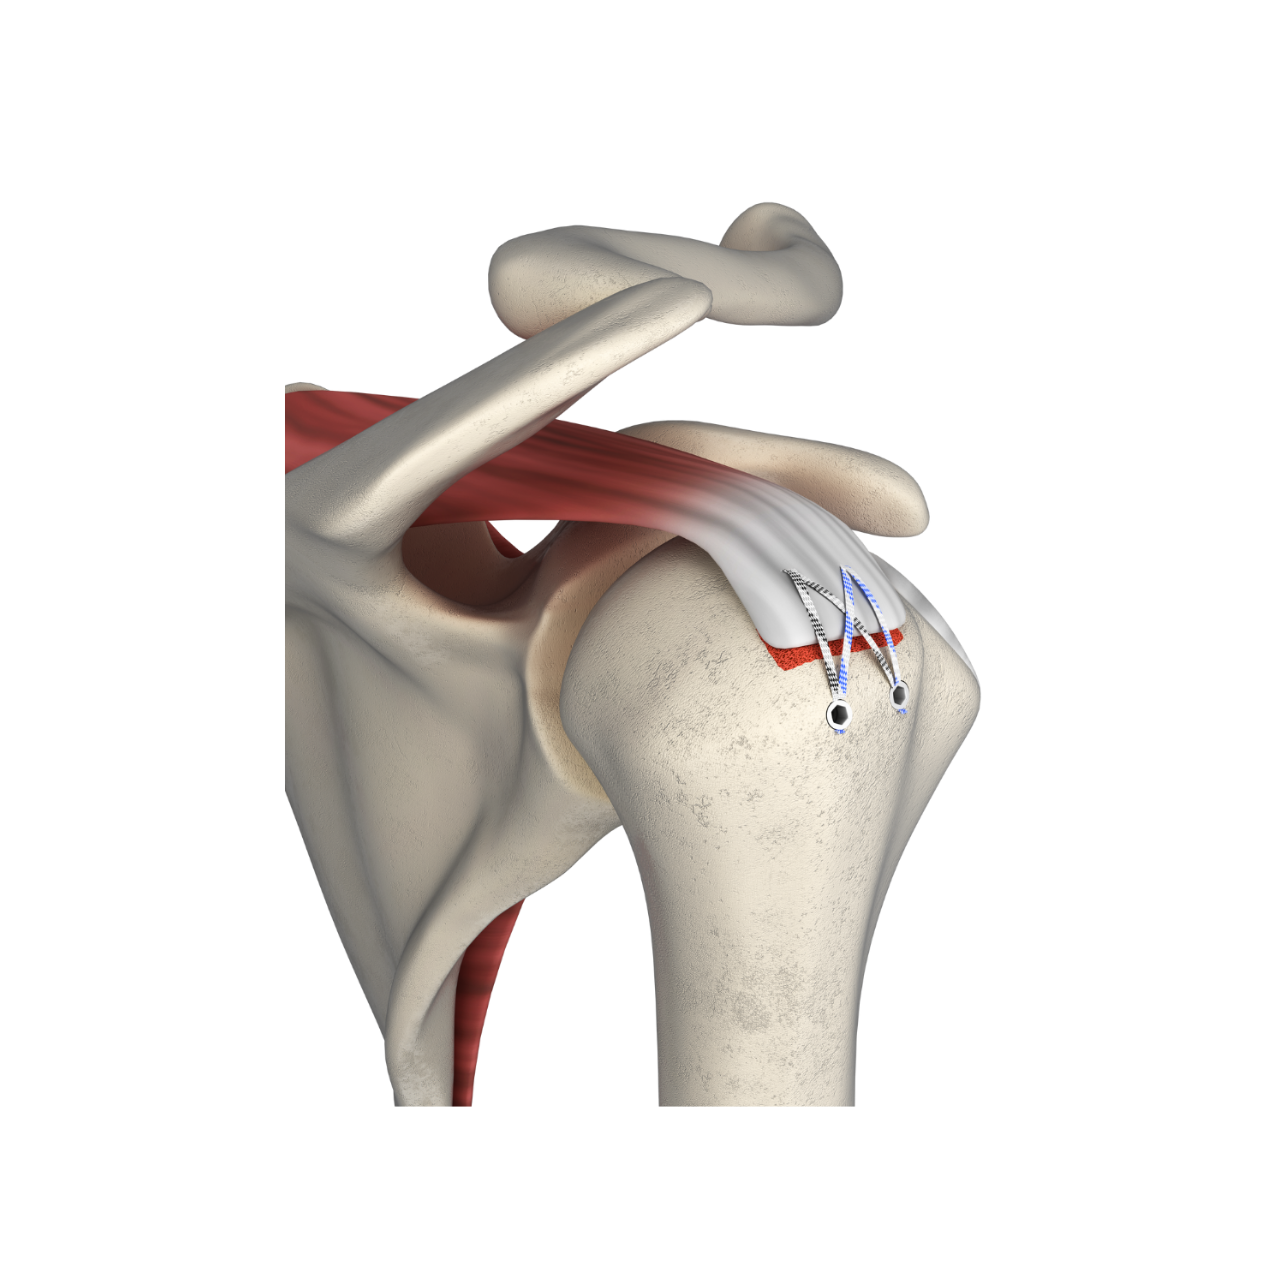

fThis technique features knotless fixation of the rotator cuff using 2 pcs of PEEK Suture Anchors (for medial row) with Fiber Tape and 2 pcs of PEEK Knotless anchors (for lateral row). Knotless PEEK Suture Anchor is available in diameter of 4.75 and 5.5mm with 1 pc of locking Fiber Tape and 1 pc of Fiber Wire. The anchor is inserted in the medial row of the rotator cuff. These Fiber Tapes are passed through the cuff tissue and then loaded into Knotless PEEK Suture Anchor and it is fixed on the lateral row using knotless anchor. The technique eliminates the need for multiple suturing passes, reducing post-operative pain and recovery time. It also increases the structural integrity of the repair, ensuring a lasting and secure fix. It is a predural time saving than the regular knot tying repairs.